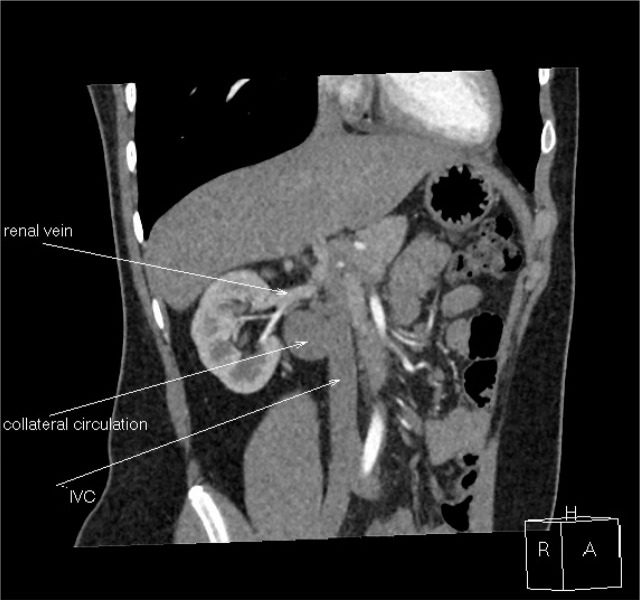

Case report: A 17-year-old boy complained of periodic abdominal pain. Abdominal ultrasonography revealed a multilocular cyst in the right kidney. Physical examination showed no abnormalities, and his blood pressure was 120/80mmHg. Abdominal ultrasonography showed a cyst measuring 36×30×25mm in the right kidney hilum. Computed tomography did not show the hepatic and suprarenal sections of the inferior vena cava. Numerous varicose-dilated collateral vessels, including renal venous vessels, were found in the right kidney hilum. The collateral vessels in the tomography matched the described in the ultrasound renal cyst. MRI confirmed IVCA with no other additional vascular abnormalities. Due to the risk of deep vein thrombosis of the lower limbs, non-pharmacological antithrombotic prophylaxis was recommended.